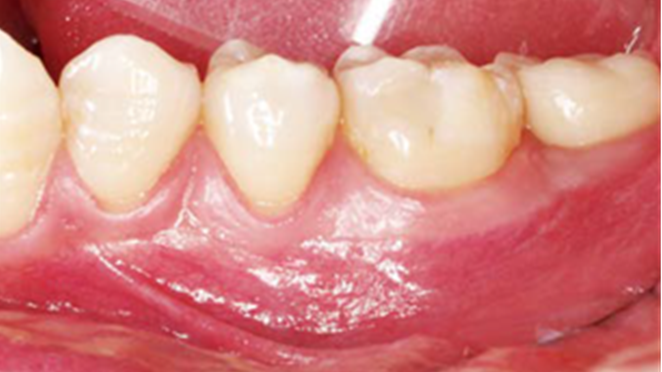

Clinical case: Single molar implant with bone augmentation

- Courtesy of Dr. Jung Sam Lee, Korea -

AnyOne, bone augmentation, osteotomy socket, peri-implant tissue, autogenous bone, GBR, single replacement, Auto-Max, Dr. Jung Sam Lee

AnyOne implant system, Auto-Max

“AnyOne implant system guarantees

excellent aesthetics & functionality for any implantologist

& any patient. ”